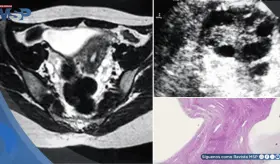

La mujer de 71 años, con antecedentes de histerectomía total y salpingooforectomía izquierda hace 30 años, presentó distensión abdominal progresiva y aumento de peso durante cuatro años.

La paciente presentaba múltiples factores de riesgo incluyendo uso de ...

Las imágenes sugerían infiltración linfomatosa, pero la esplenectomía ...